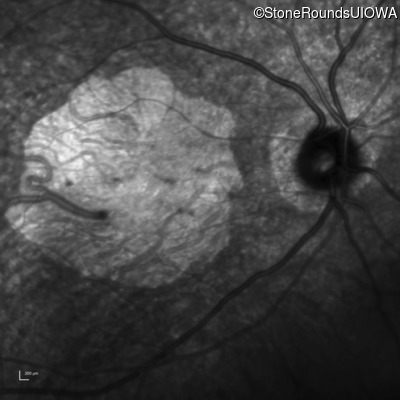

AR Stargardt Disease (IIA)

AR Stargardt Disease

ABCA4

Gly607Arg GGG>AGG

IVS30+1321 A>G

AR

Disease:

Gene:

Allele 1:

Allele 2:

Inheritance: